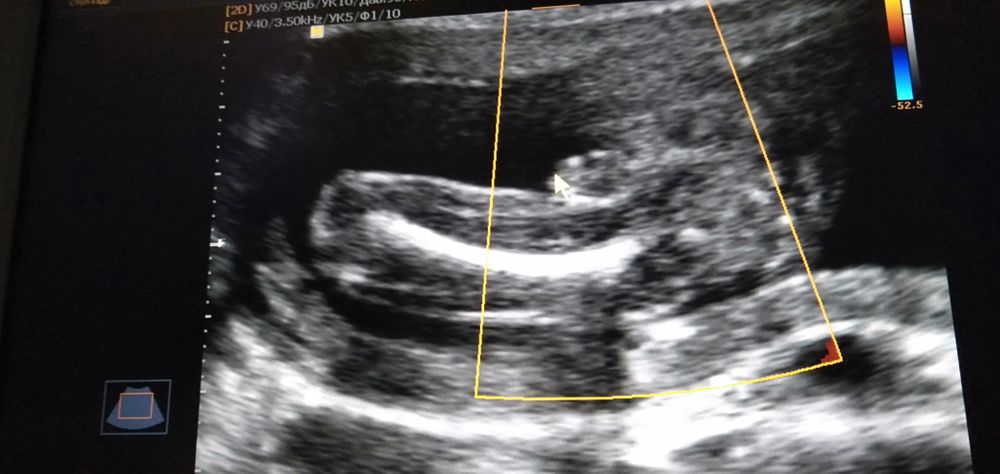

Изображение Моё УЗИ

Екатерина, пардон это вообще какая часть тела?

Елизавета, это попа и нога

Елизавета, вид снизу

Елизавета, да это ножка и попа,вид снизу

Екатерина, все рассмотрела)) Мне кажется это машонка и это мальчик)